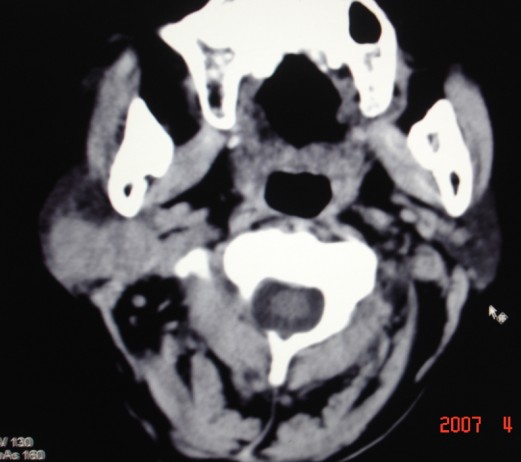

以下是引用zjzjr在2007-4-9 13:27:00的发言:[br]右侧腮腺深浅叶可见一混杂密度区,含有实性及囊性成.考虑右侧腮腺混合瘤,建议ct增强扫描。

以下是引用jiangjing在2007-4-9 15:09:00的发言:[br]考虑右侧腮腺肿瘤[混合瘤可能性大],其他待排[br]建议ct增强扫描。